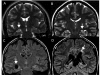

Figures